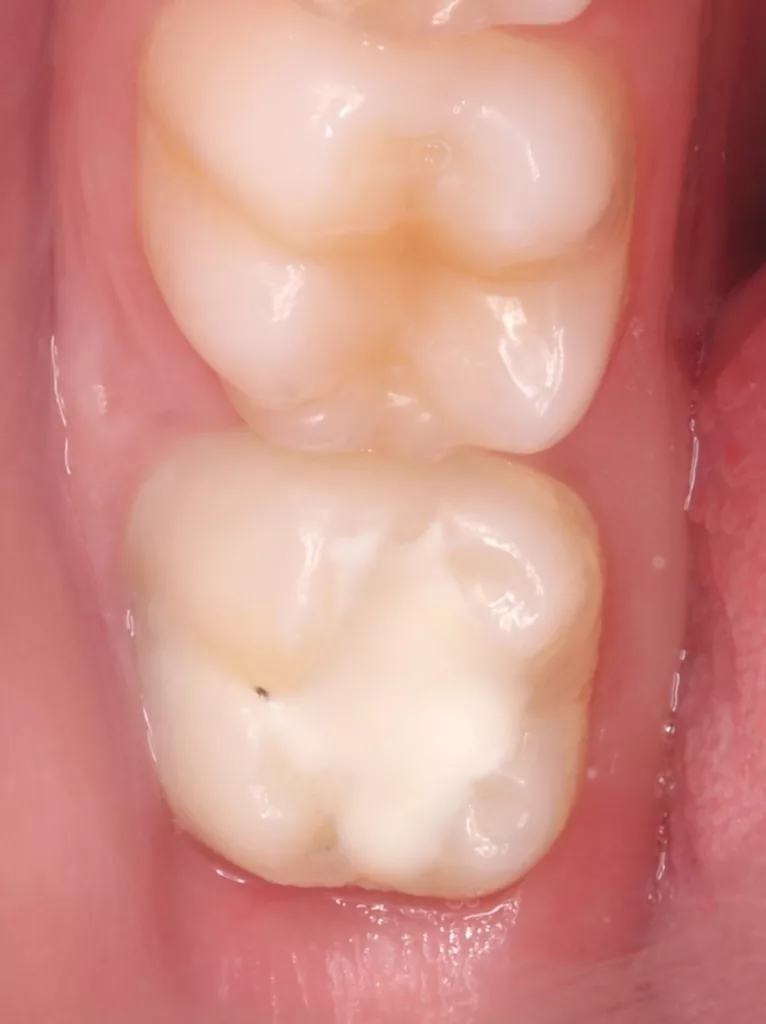

Im Rahmen der jährlichen Kontrolluntersuchung wurde bei einem achtjährigen Mädchen auf der routinemäßig angefertigten Röntgenaufnahme eine mittelgroße PEIR des Zahnes 46 (Grad 2 der Läsion nach Seow) entdeckt (Abb. 43). Die Patientin war komplett beschwerdefrei und der Zahnschmelz des betroffenen Zahnes sah intakt aus (Abb. 44 und 45). Weil auch hier der PEIR-Defekt gräulich durchschimmerte (Abb. 44 und 45) und der Zahn bereits seit einem Jahr durchgebrochen war, entschieden wir uns in diesem Fall, den Defekt klassisch mit Komposit zu restaurieren. Unter Lokalanästhesie mit Septanest 1/100 000 (Septodont, Frankreich) wurde zunächst Kofferdam mithilfe der Klammer U67 (KSK Dentech, Japan) gelegt (Abb. 45). Weder visuell noch mittels Sondierung konnte eine Verbindung zur Läsion festgestellt werden. Deswegen wurde an der Stelle, an welcher der PEIR-Defekt gräulich schimmerte, intakter Zahnschmelz der lingualen Querfissur entfernt (Abb. 46). Innerhalb der Läsion wurde nekrotisches intrakoronales Weichgewebe vorgefunden (Abb. 47), das problemlos mittels RONDOflex plus 360 (KaVo Dental, Deutschland) mit dem 27-µm-Pulver vollständig entfernt werden konnte. Der Boden des Defektes zeigte eine glatte, runde Form sowie helles, hartes und intaktes Dentin. Eine Präparation war nicht erforderlich, es wurde lediglich die Zahnschmelzkante geglättet (Abb. 48). Für die Restauration kamen erneut das Adhäsiv Optibond FL (Kerr, USA) und das Komposit Estelite ASTERIA OCE, A2B und Universal Flow AO2 (Tokuyama, Japan) zur Anwendung (Abb. 49). 6 Monate nach der Behandlung zeigte sich das Ergebnis sowohl aus klinischer als auch radiologischer Sicht stabil wie die Abbildungen 50 und 51 zeigen.